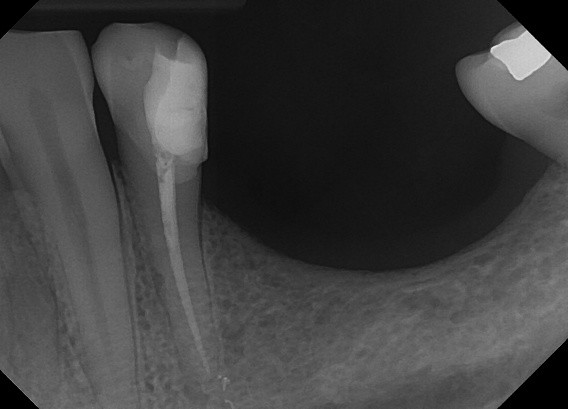

9. (Select ONE OR MORE correct answers)

Which of the following describe(s) the endodontic treatment of tooth 3.4?